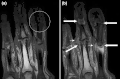

T1 weighted axial MRIs of the fingers in PsA. (a) Pre- and (b) post-contrast showing dactylitis due to flexor tenosynovitis at the second finger with enhancement and thickening of the tendon sheath (large arrow), and synovitis at proximal interphalangeal joint (small arrow). -

T1-weighted semi-coronal MRI of sacroiliac joints (a) before and (b) after contrast showing active sacroiliitis (arrow). -

Coronal T1-weighted MRI of fingers in PsA. (a) Pre- and (b) post-contrast showing active synovitis at proximal and distal interphalangeal joints (large arrows), joint space narrowing, bone proliferation at proximal interphalangeal joint, erosions at distal interphalangeal joint (white circle), enthesitis medial to proximal interphalangeal joints. -